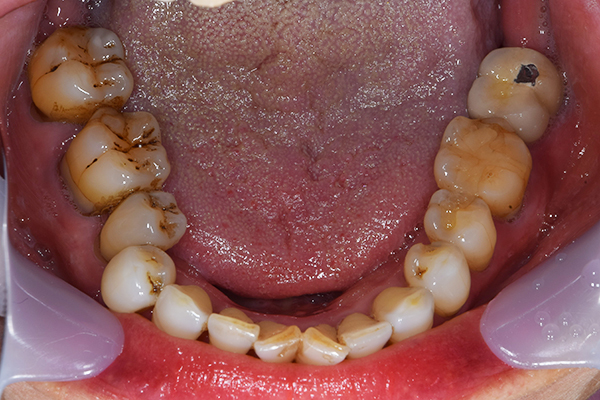

上下の入れ歯が外れやすくなったということでいらっしゃいました。 顎の骨はしっかりしていましたので、精密な型取りさえすればしっかりした入れ歯がつくれると思いました。 また下には6本歯が残っていましたが、虫歯になっている歯もありました。 かぶせ物のなかで大きな虫歯があった歯があり、1本だけ残せない状態でした。

上の入れ歯は確かに吸着は甘くなっていました。 また下の入れ歯はバネの一部が壊れており、安定感がなくなっていました。

お口の中に入れた状態です。 見た目も最初とほとんど変わることなく作成できました。 維持や吸着に関しても問題ないようでした。